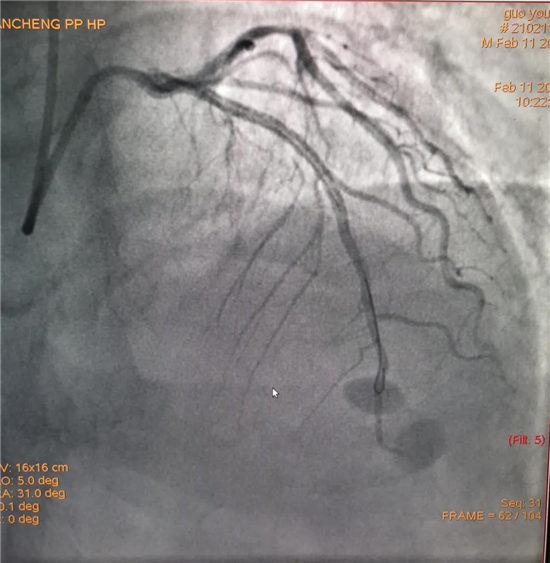

除夕,郭先生無明顯誘因突發(fā)胸痛,120急救人員到達(dá)現(xiàn)場,心電圖顯示:竇性心律完全性束支傳導(dǎo)阻滯。信息立刻發(fā)送到胸痛中心介入微信群中,心內(nèi)科值班醫(yī)生初步診斷為急性廣泛前壁心肌梗死,必須盡快進(jìn)行急診支架治療,開通血管。值班醫(yī)生電話指導(dǎo)院前治療,并立即啟動胸痛綠色通道,24小時備班的介入治療團(tuán)隊立即到位,9:30患者被送到導(dǎo)管室行冠脈介入診療,9:40急診PCI手術(shù)隨之開始,冠脈造影檢查提示左前降支閉塞,植入支架,堵塞的血管被順利打通,患者癥狀緩解,手術(shù)非常成功,10:20患者被送往病房進(jìn)一步治療。

大年初一,王女士在中午休息時無明顯誘因出現(xiàn)上腹部疼痛,伴瀕死感、大汗、劇烈嘔吐,當(dāng)?shù)卦\所以“胃炎”治療無緩解,自行來我院就診。在急診內(nèi)科快速完成心電圖等相關(guān)檢查后,心電圖示:竇性心律,部分導(dǎo)聯(lián)明顯異常,經(jīng)心內(nèi)科值班醫(yī)生初步診斷,該患者為急性冠脈綜合征,與患者家屬溝通行急診PCI的相關(guān)事宜,溝通中了解患者高血壓、2019年因急性心肌梗死在周口市中心醫(yī)院性急診冠脈介入植入1枚支架等高風(fēng)險因素。風(fēng)險與生命孰重,21:50 患者到導(dǎo)管室行急診PCI治療,造影提示右冠閉塞。22:18 導(dǎo)絲通過閉塞段,后植入支架一枚,血管再通。22:45手術(shù)結(jié)束,送往CCU觀察治療。